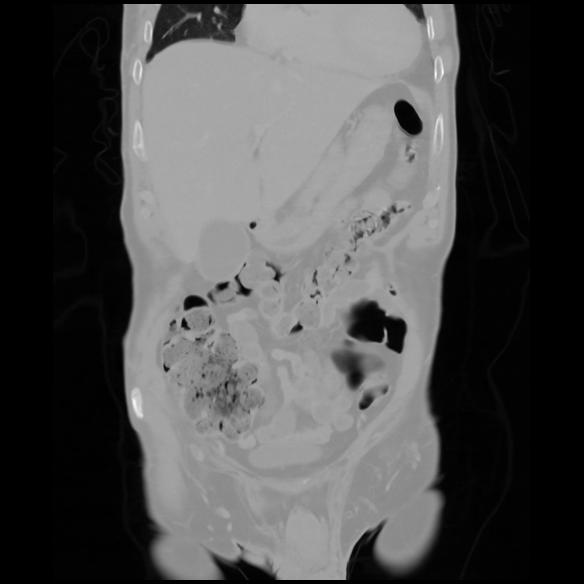

6 CUERPO,CE,Coronal,3.000,CUERPO,Coronal,